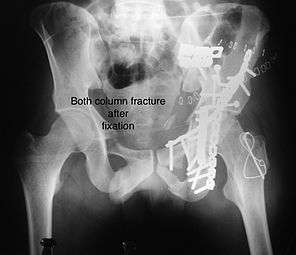

Combined both column fractures

These are the most complex injuries. Here the weight bearing roof or dome of the acetabulum is a floating piece. This adds to complexity of management.

Cause: Combination of forces acting on the hip though the femoral head

Associated injury: Sciatic nerve, may be femoral nerve or vessels

How to diagnose: all three x-ray views plus CT scan is a must for diagnosis and management of this complex injury

Treatment: like any other acetabular fracture, if the femoral head is dislocated out of the socket, early reduction into socket is a priority. Non operative treatment rarely gives satisfactory result. If the patient is unfit to undergo major surgery due to any reason, longitudinal traction to achieve secondary congruence of hip may help to restore hip function, though partially.

Surgical management is ideal. The choice of approach rests with the surgeon, but going from front, or anterior approach is preferred. The posterior injury may be tacked with anterior approach by experienced surgeon.

Post-surgery treatment: depending on the stability achieved, the person may be allowed standing and walking with help of support for about six to eight weeks.

Full function may return in about three months.